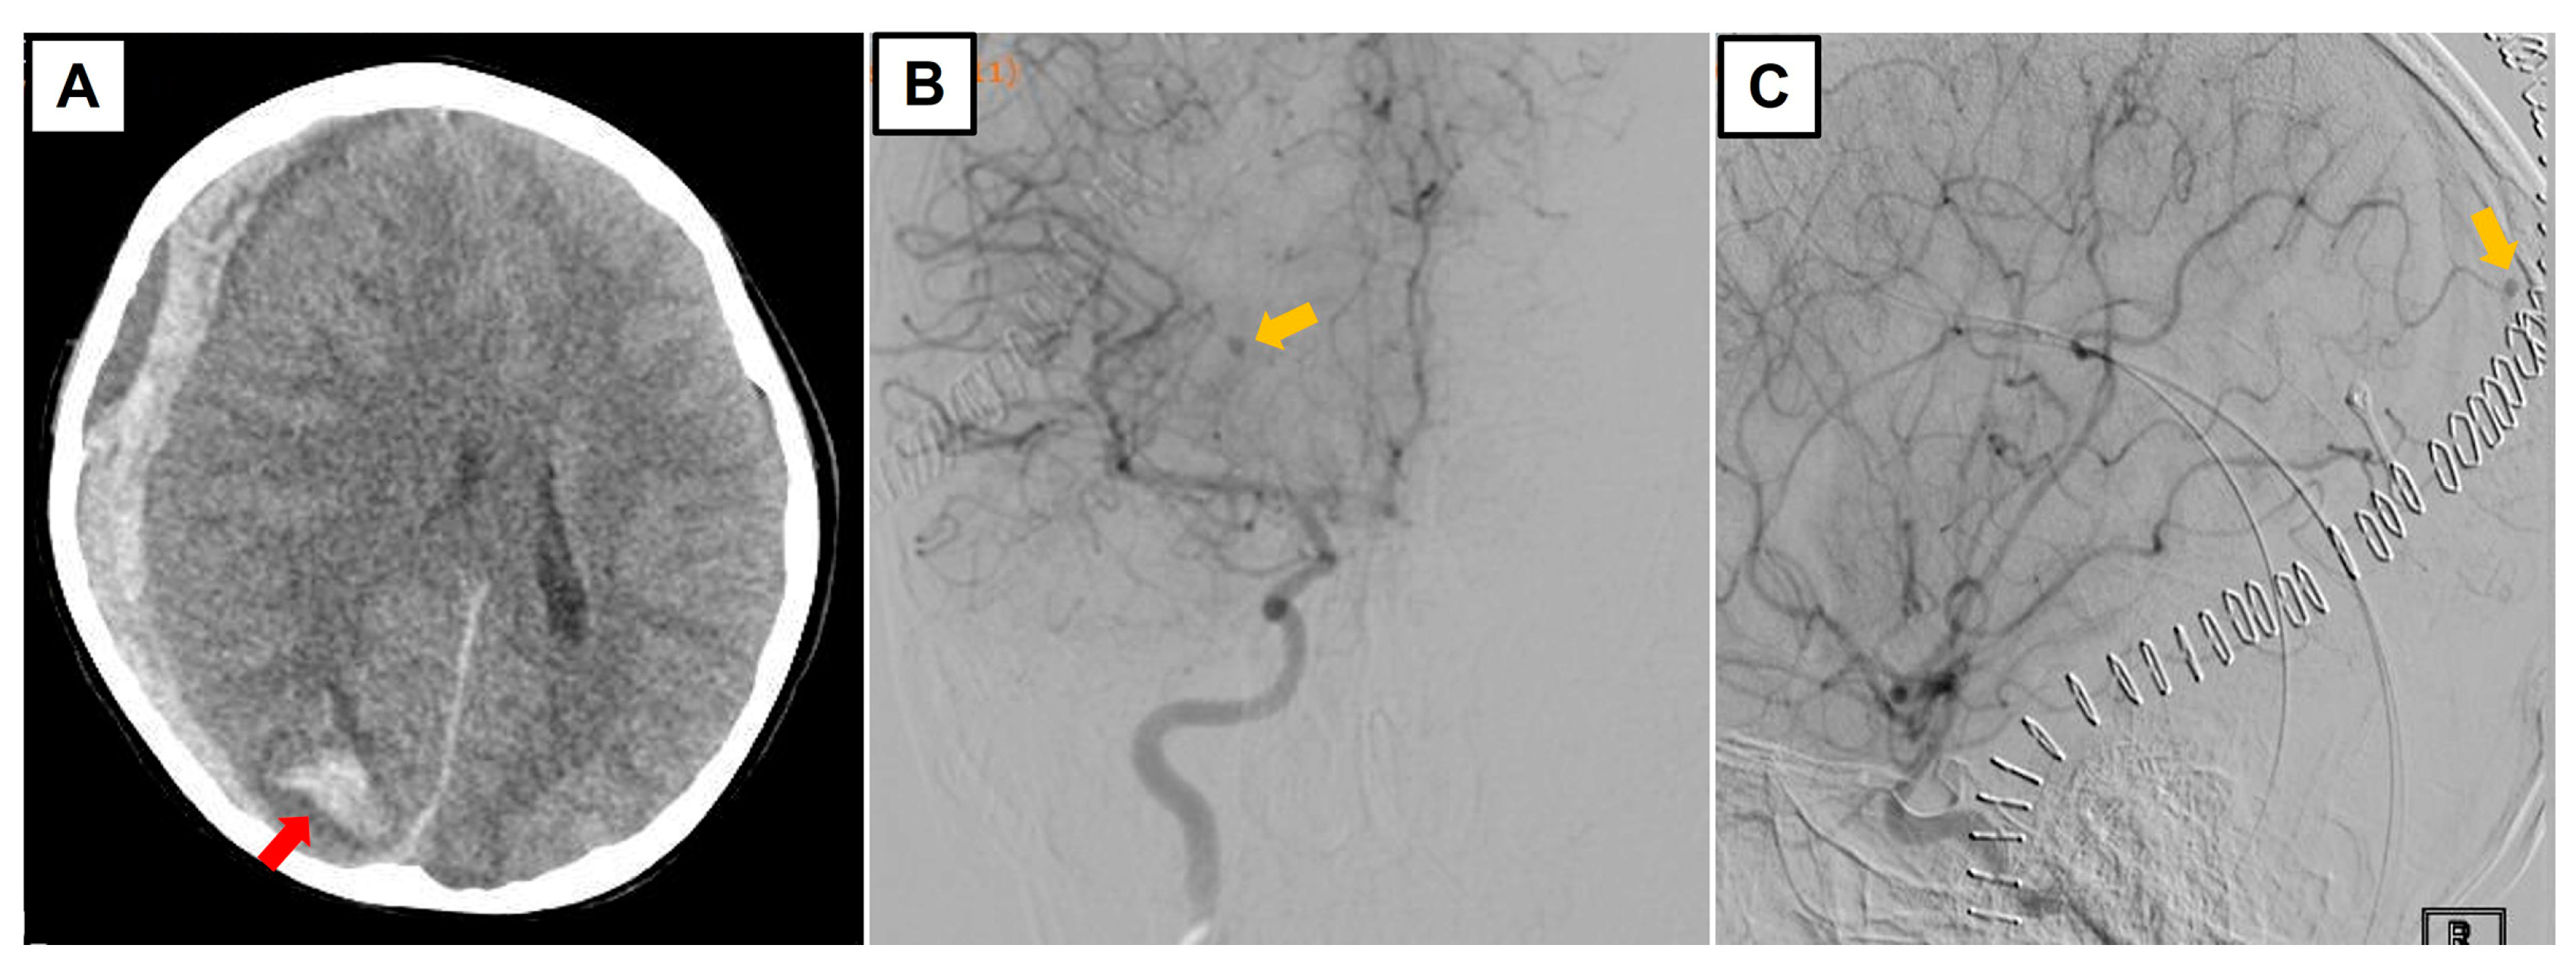

3.4. Illustrative Case Example: Challenging Diagnosis